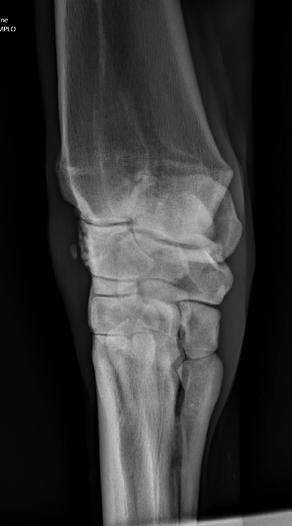

Radiographs of a knee (left) and a hock (right), showing osteoartritis in a horse.

Images courtesy of Dr. McClure